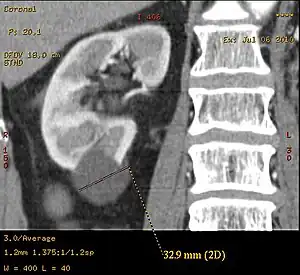

Simple renal cyst.jpg

Simple renal cyst